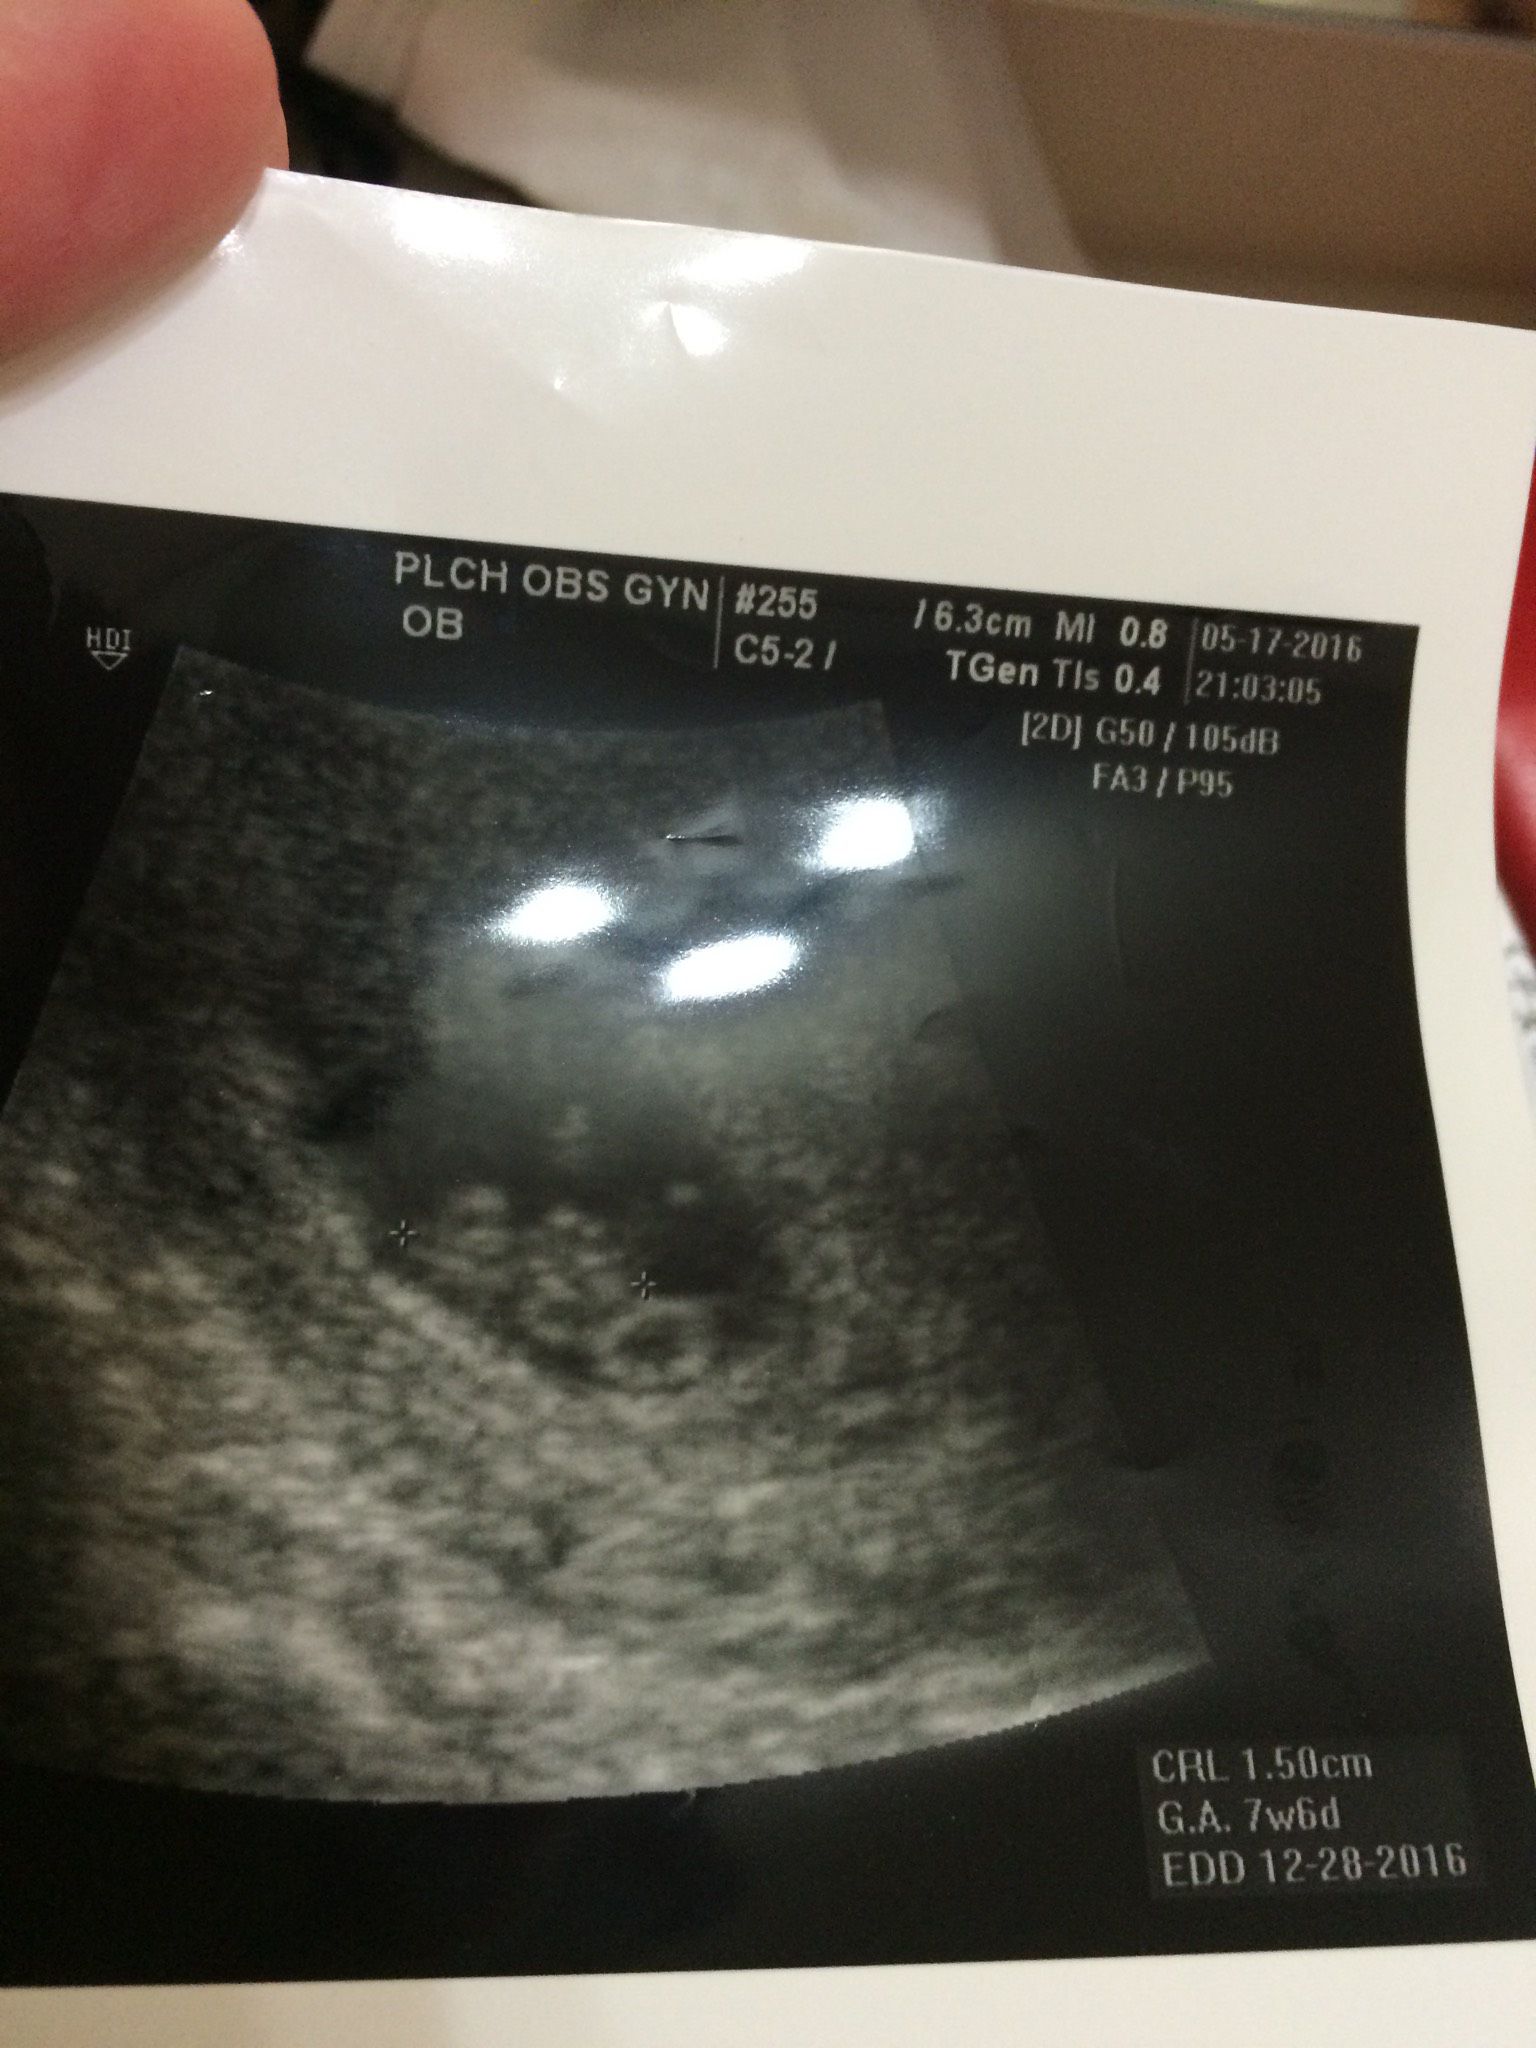

8週超音波 看的出來男女嗎